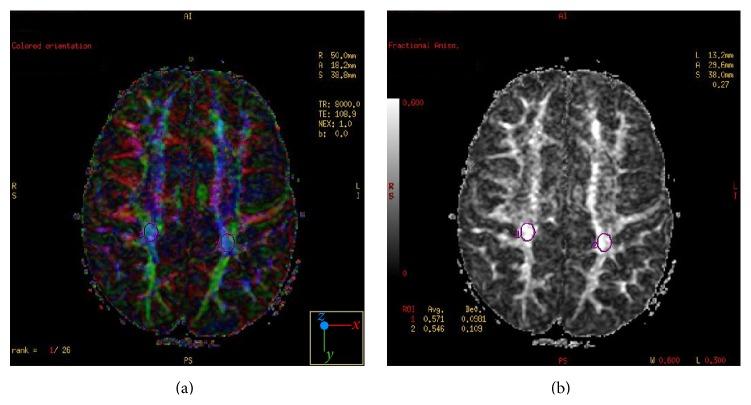

To assess the relationship between stereoscopic vision, visual perception, and microstructure of the corpus callosum (CC) and occipital white matter, 61 children born with a mean birth weight of 1024 g (SD 270 g) were subjected to detailed ophthalmologic evaluation, Developmental Test of Visual Perception (DTVP-3), and diffusion tensor imaging (DTI) at the age of 4.

Abnormal stereoscopic vision was detected in 16 children. Children with abnormal stereoscopic vision had smaller CC (CC length: 53 ± 6 mm versus 61 ± 4 mm; p < 0.01; estimated CC area: 314 ± 106 mm(2) versus 446 ± 79 mm(2); p < 0.01) and lower fractional anisotropy (FA) values in CC (FA value of rostrum/genu: 0.7 ± 0.09 versus 0.79 ± 0.07; p < 0.01; FA value of CC body: 0.74 ± 0.13 versus 0.82 ± 0.09; p = 0.03). We found a significant correlation between DTVP-3 scores, CC size, and FA values in rostrum and body. This correlation was unrelated to retinopathy of prematurity.

为评估立体视觉、视觉感知与胼胝体(CC)及枕叶白质微观结构之间的关系,对61名平均出生体重为1024克(标准差270克)的儿童在4岁时进行了详细的眼科评估、视觉感知发育测试(DTVP - 3)和扩散张量成像(DTI)。

16名儿童检测出立体视觉异常。立体视觉异常的儿童胼胝体较小(胼胝体长度:53±6毫米对61±4毫米;p<0.01;估计胼胝体面积:314±106平方毫米对446±79平方毫米;p<0.01),胼胝体的分数各向异性(FA)值较低(喙部/膝部的FA值:0.7±0.09对0.79±0.07;p<0.01;胼胝体体部的FA值:0.74±0.13对0.82±0.09;p = 0.03)。我们发现DTVP - 3得分、胼胝体大小与喙部和体部的FA值之间存在显著相关性。这种相关性与早产儿视网膜病变无关。